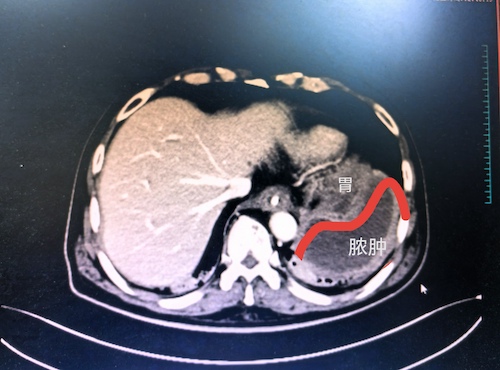

来自中南大学湘雅三医院重症医学科的邢伟,作为结对帮扶湘西自治州人民医院重症医学科的执行主任,在对一例从花垣县转来的危重患者组织全院大会诊,会诊时发现该患者为左侧膈下脓肿,与脾脏和肺脏紧邻,彩超定位不明确。临床上治疗腹腔脓肿多采用B超引导下穿刺引流,但是该方法对位置较深,或周围血管、脏器关系密切的积脓患者,定位的准确性受到影响,而CT定位穿刺,可标记最佳穿刺层面、角度、进针点及深度等,进针路径选取为路径最短、路径间隙较宽,避开重要脏器及血管,从而使穿刺引流具有效果确切、创伤小、安全性高等优点。随后,邢伟与湘西自治州人民医院重症医学科的医生一同为该患者迅速制定后续治疗方案,于4月24日,在余灿博士配合下成功为该患者完成CT引导下脾周脓肿穿刺引流术。